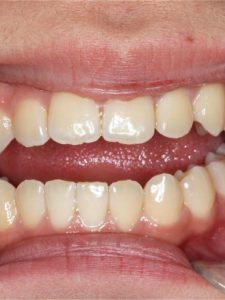

Jaw Repositioning (Orthognathic) Surgery

Before and After Images